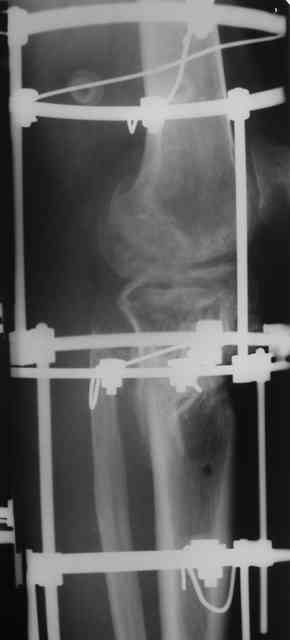

Р-граммы и фото за 4.05.2007 - 7-е сутки после операции.

Ход операции - линейным разрезом по передней поверхности голени обнажена зона ложного сустава большеберцовой кости. От кости отсепарованы медиально м/ткани. Из зоны ложного сустава убраны рубцовые ткани, мобилизован дистальный отломок. По передней поверхности удалены два осколка, связанных грануляциями. Произведено удаление грануляционной ткани из проксимального отломка (на вид сине-серого цвета), "чистого" гноя не было. Затем произведено наложение аппарата и репозиция отломков. По передне-медиальной поверхности образовался дефект до 4х2х2 см + полость в проксимальном отломке. Удаленные осколки очищены от грануляций, уложены в место дефекта, зажаты между отломками. После иссечения раны по передней поверхности, находящейся рядом с операционной раной, последняя ушита с большим натяжением.

Перелом мыщелка сросся. Проксимальный отломок очень порозный.

Аппарат видел, репозиции не заметил. О "наложенном" аппарате: спицы в проксимальном отломке б\берцовой кости проведены очень низко, и опять только две, как и в первом аппарате. Почему только одна спица в дистальном парафрактурном кольце? Проксимальная база на бедре должна улучшить стабильность проксимального фрагмента tibia? Ничего подобного двумя спицами в одной базе при таком длинном рычаге вы не добьетесь, а вот совсем потерять движения в коленном суставе они почти гарантируют.

О репозиции: мыщелок сросся и слава Богу, но основные отломки фиксированы в вальгусном положении, собственно как и было, это критично. В чем состояла репозиция?